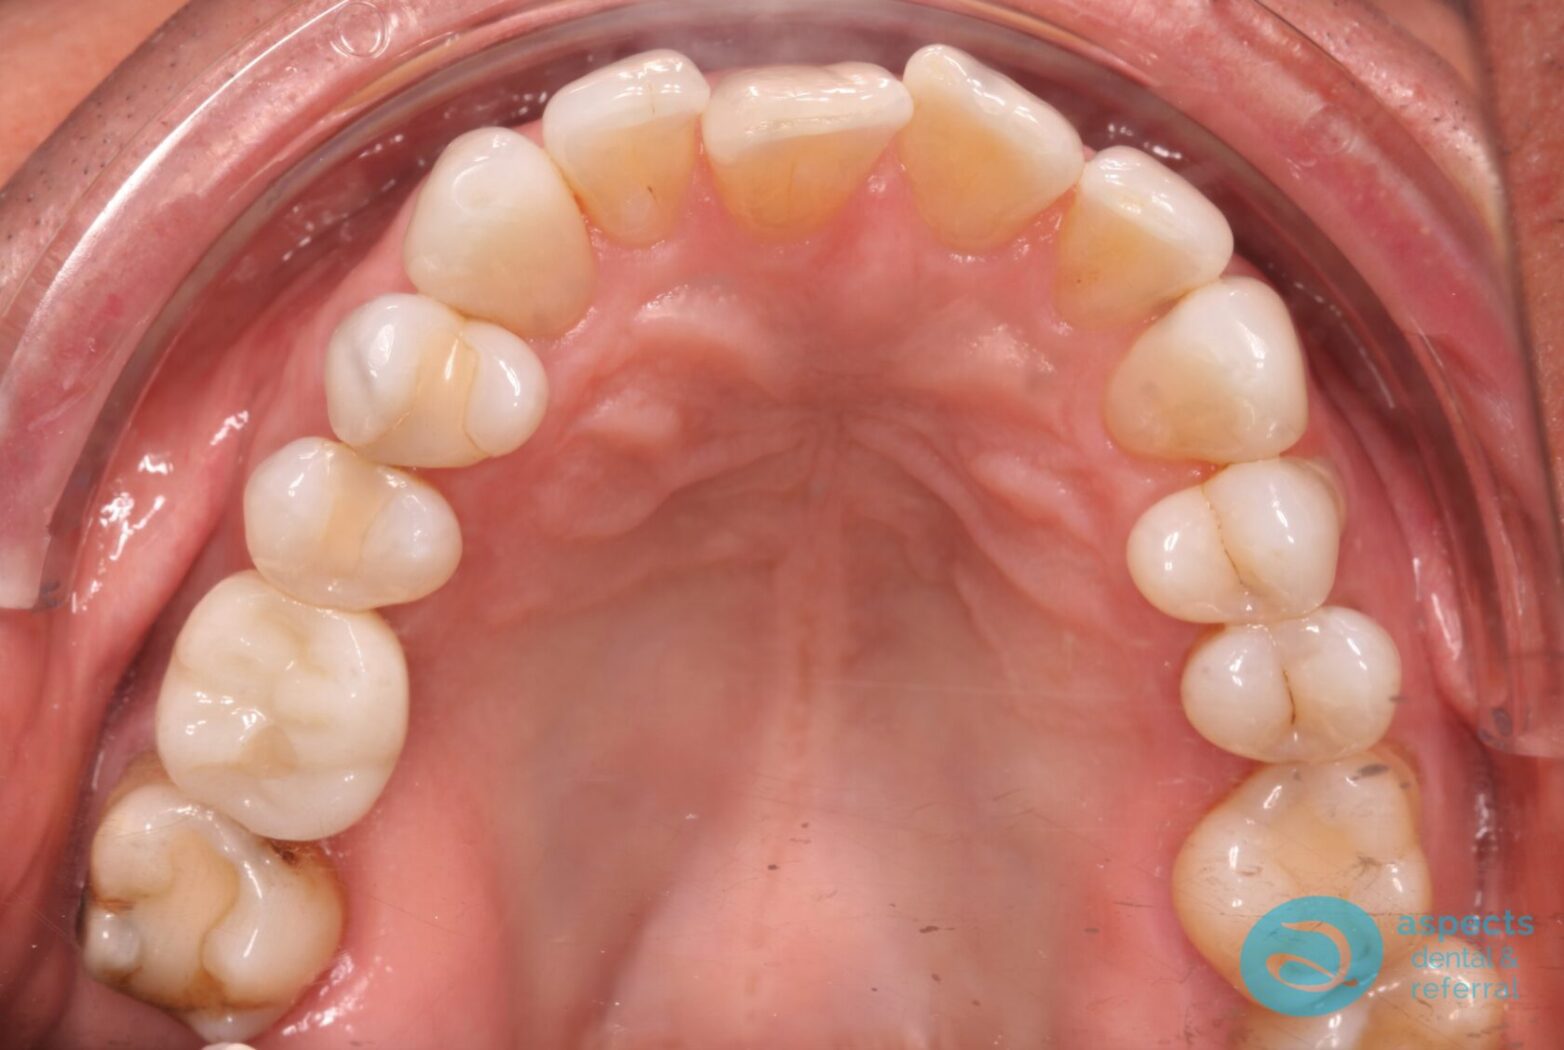

After Dental Implant Photo